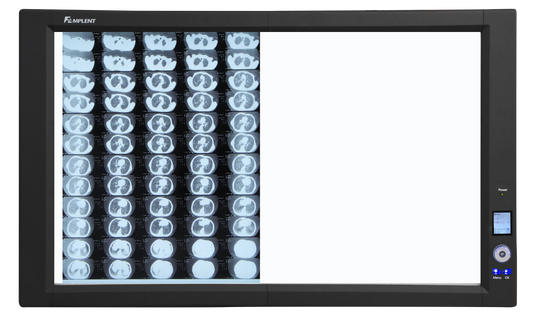

Wolf X-Ray offers a complete line of x-ray illuminators to satisfy your specific need. From a basic two-bulb desktop viewer, to top-of-the-line mammography and orthopedic imaging viewers, Wolf has the right illuminator for your imaging department. We can even create a "bank" of up to 6 viewers, or a "double bank" of 6 over 6 viewers.

Trimline LED Illuminator